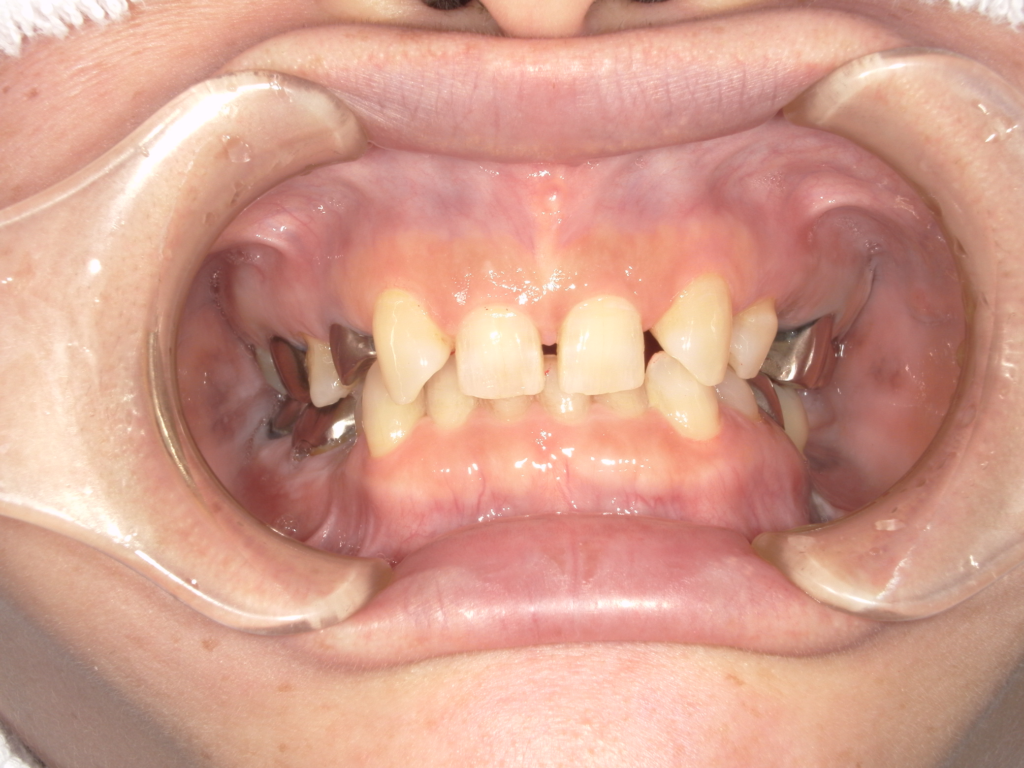

T様インプラント実例 #1

術前の写真は途中まで治療が進んでいまして、インプラントの仮歯が入っている状態です。

上の前歯4本をインプラントで治療しています。

被せものは全てセラミックスで治しています。

治療前

治療後